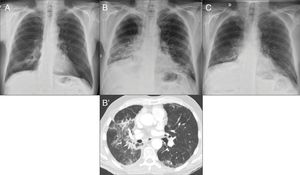

Figure 2.Intestinal perforation associated with VEGF-targeted therapy. Case 1 (A): 46-year-old woman with ovarian cancer being treated with bevacizumab. Computed tomography (CT) shows pneumoperitoneum (arrow) and free fluid (star) in the context of an intestinal obstruction. This obstruction was not very serious; the intestinal wall was probably weakened due to bevacizumab. Case 2 (B–D): 71-year-old male on second-line treatment with a paclitaxel-ramucirumab regimen for metastatic recurrence of gastric adenocarcinoma. (B) CT obtained during admission due to pyrexia and abdominal pain after the 2nd cycle: new-onset ascites and thickening of the transverse, descending and sigmoid colon in relation to colitis (arrow). Corticosteroid treatment and a watch-and-wait approach adopted as the patient showed clinical improvement. (C and D) CT of abdomen and pelvis performed one week later due to clinical worsening: persistence of the colitis (arrow) observed, as well as new-onset pneumoperitoneum (star) due to intestinal perforation.